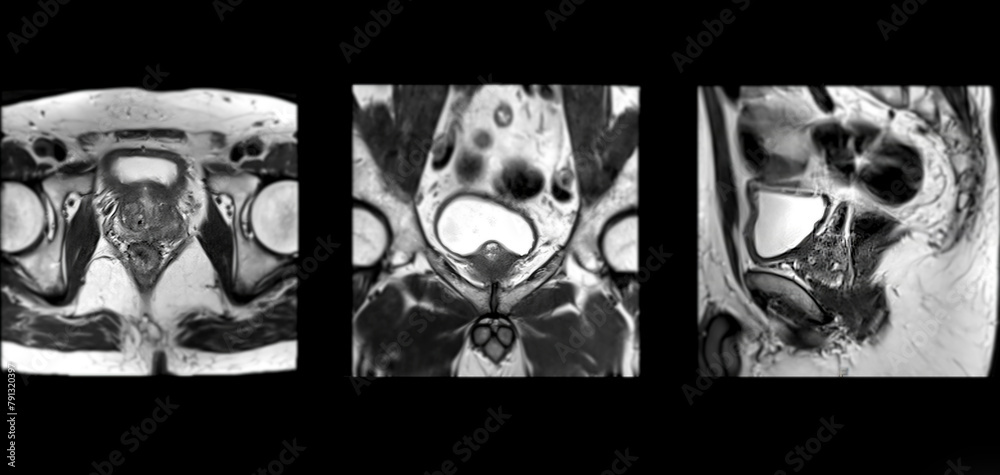

Perineale MRT-Fusionsbiopsie der Prostata

Bei einem Verdacht auf Prostatakrebs setzen wir in unserer Praxis sehr präzise Methoden ein. Die sogenannte perineale MRT-Fusionsbiopsie erlaubt es uns, auffällige Bereiche, die zuvor in einer speziellen Prostata-MRT sichtbar gemacht wurden, gezielt zu untersuchen. Über einen kleinen Zugang im Bereich zwischen Hodensack und After – dem sogenannten Damm oder Perineum – entnehmen wir unter örtlicher Betäubung mit einer dünnen Nadel Gewebeproben. Durch die Kombination von MRT-Bildgebung und Ultraschall führen wir die Nadel genau dorthin, wo der Verdacht am größten ist. Das Verfahren ist sicher, schonend und deutlich zielgenauer als herkömmliche Biopsien.